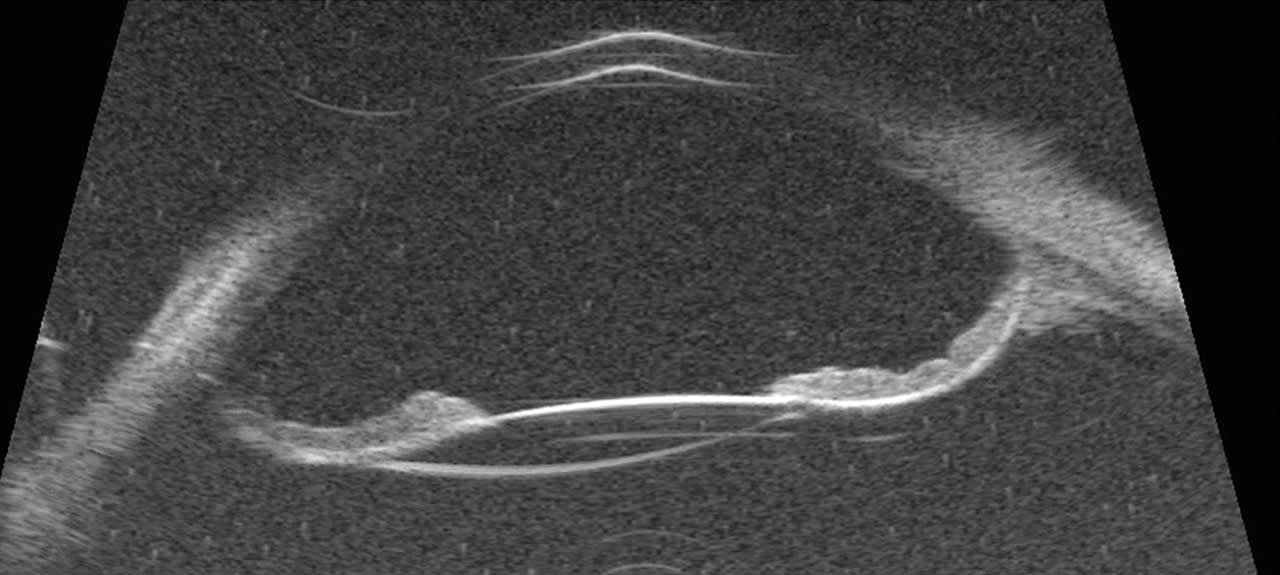

The crux of the matter, and the key to managing any eye whether long or short, is understanding the dynamic relationship between the iris, the lens-capsule complex, and the hyaloid face (Figure 1). A short eye will tend to push forward, with fluid being directed behind the iris and/or between the posterior capsule and hyaloid face (aqueous misdirection), pushing the entire capsular complex forward, shallowing the anterior chamber, and causing iris prolapse. A long eye will have a larger volume of anterior chamber, an iris prone to posterior bowing, and bouncy zonules. This leads to overfill of the anterior chamber, pushing the iris back toward the anterior lens capsule, causing posterior pupillary block due to a posteriorly bowed iris, pushing the whole capsular complex posteriorly stressing zonules.

Figure 1. In long eyes, posterior iris bowing and overfill push the capsular complex backward, stressing zonules and creating posterior pupillary block.